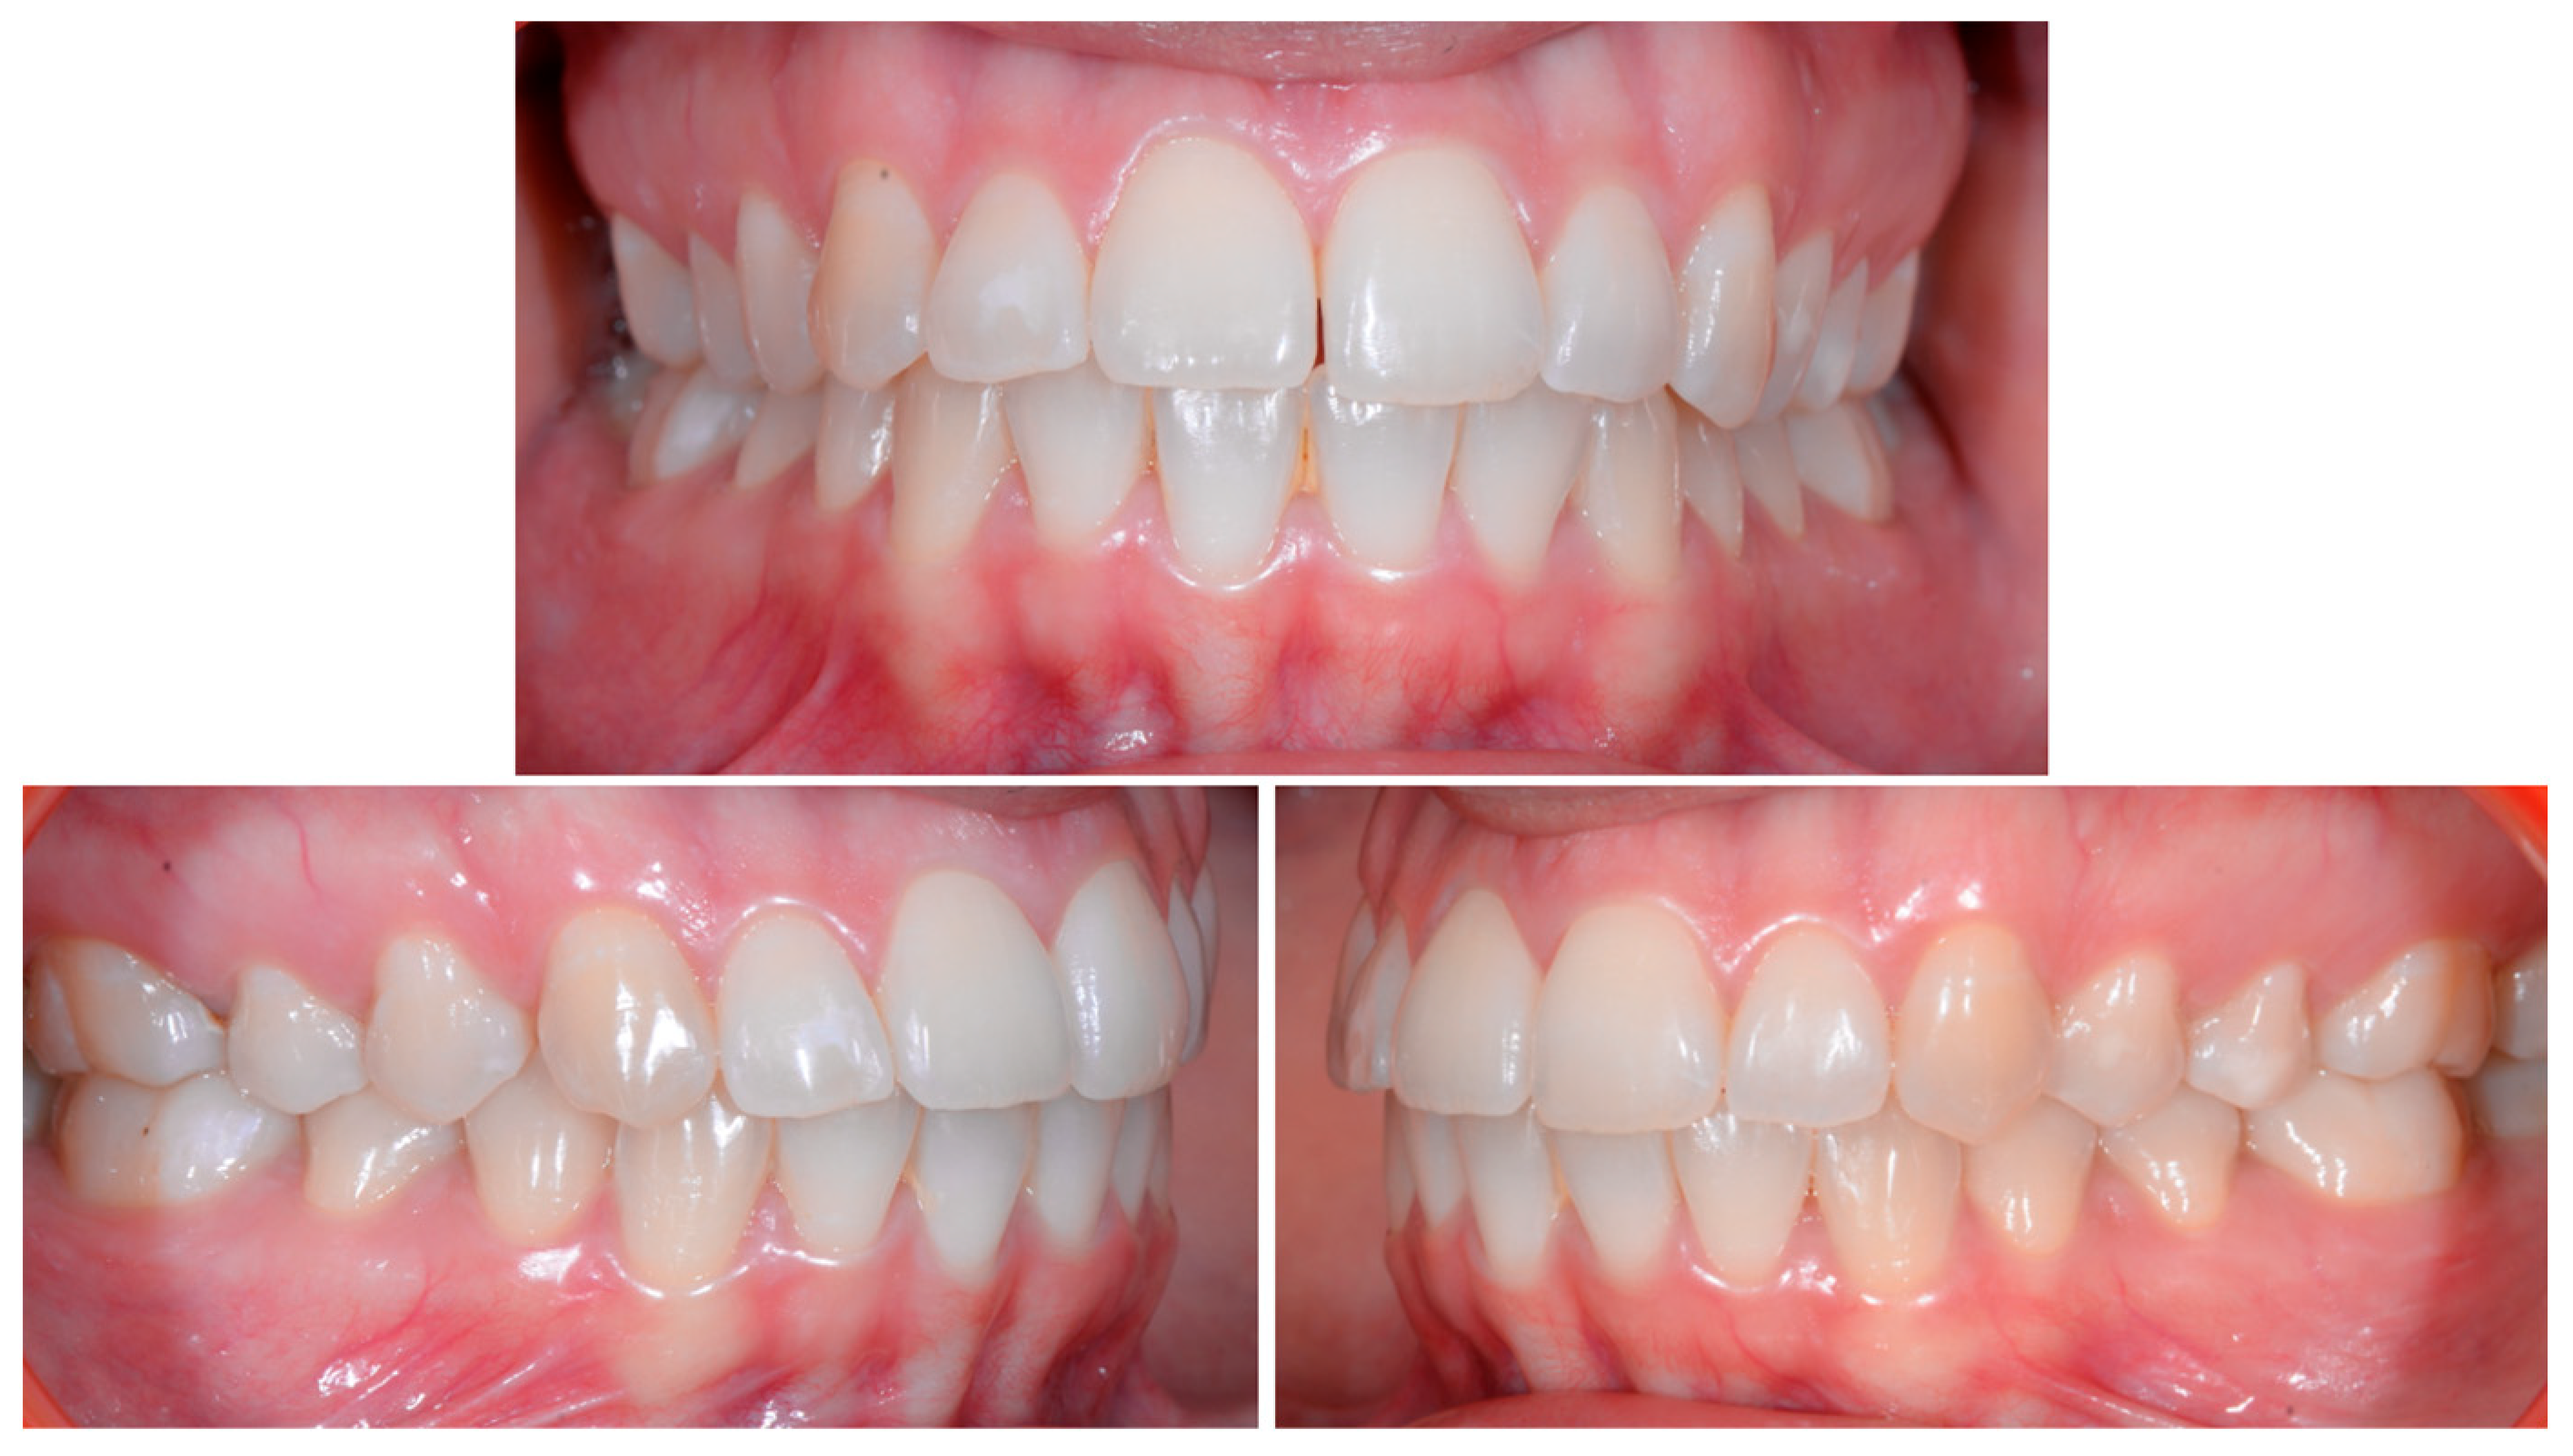

A 22-year-old female patient in good health had a consultation because she was concerned about the “root prominence” of tooth 41. She wore a mandibular retainer wire when she was 16 years old at the end of her orthodontic treatment. She has good oral hygiene, despite the presence of tartar between 31 and 41, and a right and left Class I with a slight deviation of the midlines (Figure 1).

Early wire syndrome. Frontal and lateral views.

A 26-year-old female patient was referred by her general dentist for suspected wire syndrome. Orthodontic treatment had been performed 10 years previously, and bonded restorations had been fitted at the end of the treatment. The patient mentioned several episodes of breakage/adhesion, without further details. She has good oral hygiene and a right and left Class I (Figure 5).

Intermediate wire syndrome. Frontal and lateral views.